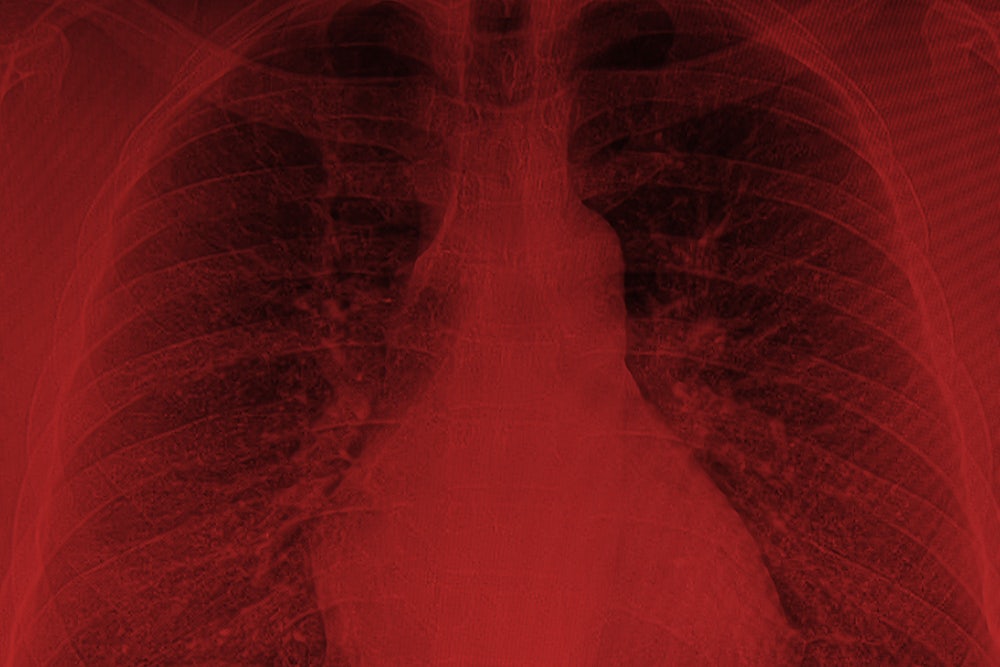

It didn’t take long for soldiers to begin to fall ill. As early as 2004, veterans who had served near burn pits began complaining of a complex and enigmatic constellation of symptoms: asthma, sinusitis, bronchitis, unexplained diarrhea, persistent runny nose or cough, severe headaches and abdominal pain, ulcers, weeping lesions on the extremities, chronic infections. Many coughed up black mucus, which they called “plume crud,” “black goop,” or “Iraqi crud.” Some developed cancers—tumors grew on their lungs, brains, bone, and skin—including leukemia. Others suffered from severe respiratory conditions, including chronic obstructive pulmonary disease and constrictive bronchiolitis, a rare and often fatal lung disorder for which there is no treatment.

Finally, a doctor at National Jewish Health in Denver referred him to Robert Miller, a pulmonary specialist at Vanderbilt University who had conducted a study on veterans from Iraq and Afghanistan with post-deployment respiratory problems. Like Baca, many of the soldiers had been exposed to the burn pits. When Miller did biopsies on the vets, he found that a high percentage of them had constrictive bronchiolitis, an incurable and often terminal illness. “It’s an untreatable disease,” Miller said at the time. “We don’t know what’s going to happen to these people down the road.”

In 2009, Jessey and Maria arranged to visit Miller in Nashville. But before they left, they learned that their insurance wouldn’t pay for the visit because it was out of network. Baca went to Vanderbilt anyway. Miller did a lung biopsy. The results were as Baca feared: He had constrictive bronchiolitis. He was going to die.

Miller’s study was published in 2011 in the New England Journal of Medicine. In a related paper, he observed that constrictive bronchiolitis “rarely occurs in otherwise healthy and athletic individuals. It is known to result from toxic inhalation.” He also noted that researchers at National Jewish Health in Denver found similar patterns of constrictive bronchiolitis among soldiers exposed to burn pits.

In June 2015, the VA finally published findings drawn from the burn-pit registry, based on questionnaires completed by 27,000 veterans who said they had been exposed to burn pits. (Nearly all of the vets also reported being exposed to dust storms at some point during their deployment.) Those exposed to burn pits suffered from higher rates of asthma, emphysema, and rare lung disorders. Thirty percent had been diagnosed with respiratory diseases, including serious disorders like chronic obstructive pulmonary disease and chronic bronchitis. Three hundred and sixty five veterans said they had been diagnosed with constrictive bronchiolitis or idiopathic pulmonary fibrosis, another incurable lung disease, typically not found in young, fit populations.